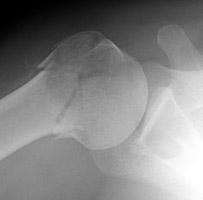

Two views of the right shoulder in this post-traumatic patient with a fracture of the proximal humerus. Note the downward displacement of the humerus and it's relation to the acromio-clavicular joint and the glenoid. The drooping shoulder occurs following fracture of the surgical neck and may be secondary to hemarthrosis or musculoligamentous injury. Other non-traumatic causes such as stroke and brachial plexus compromise from a tumor have been described as well.

AP shoulder - Click on the image for a larger versionAAxillary view - Click on the image for a larger versionB